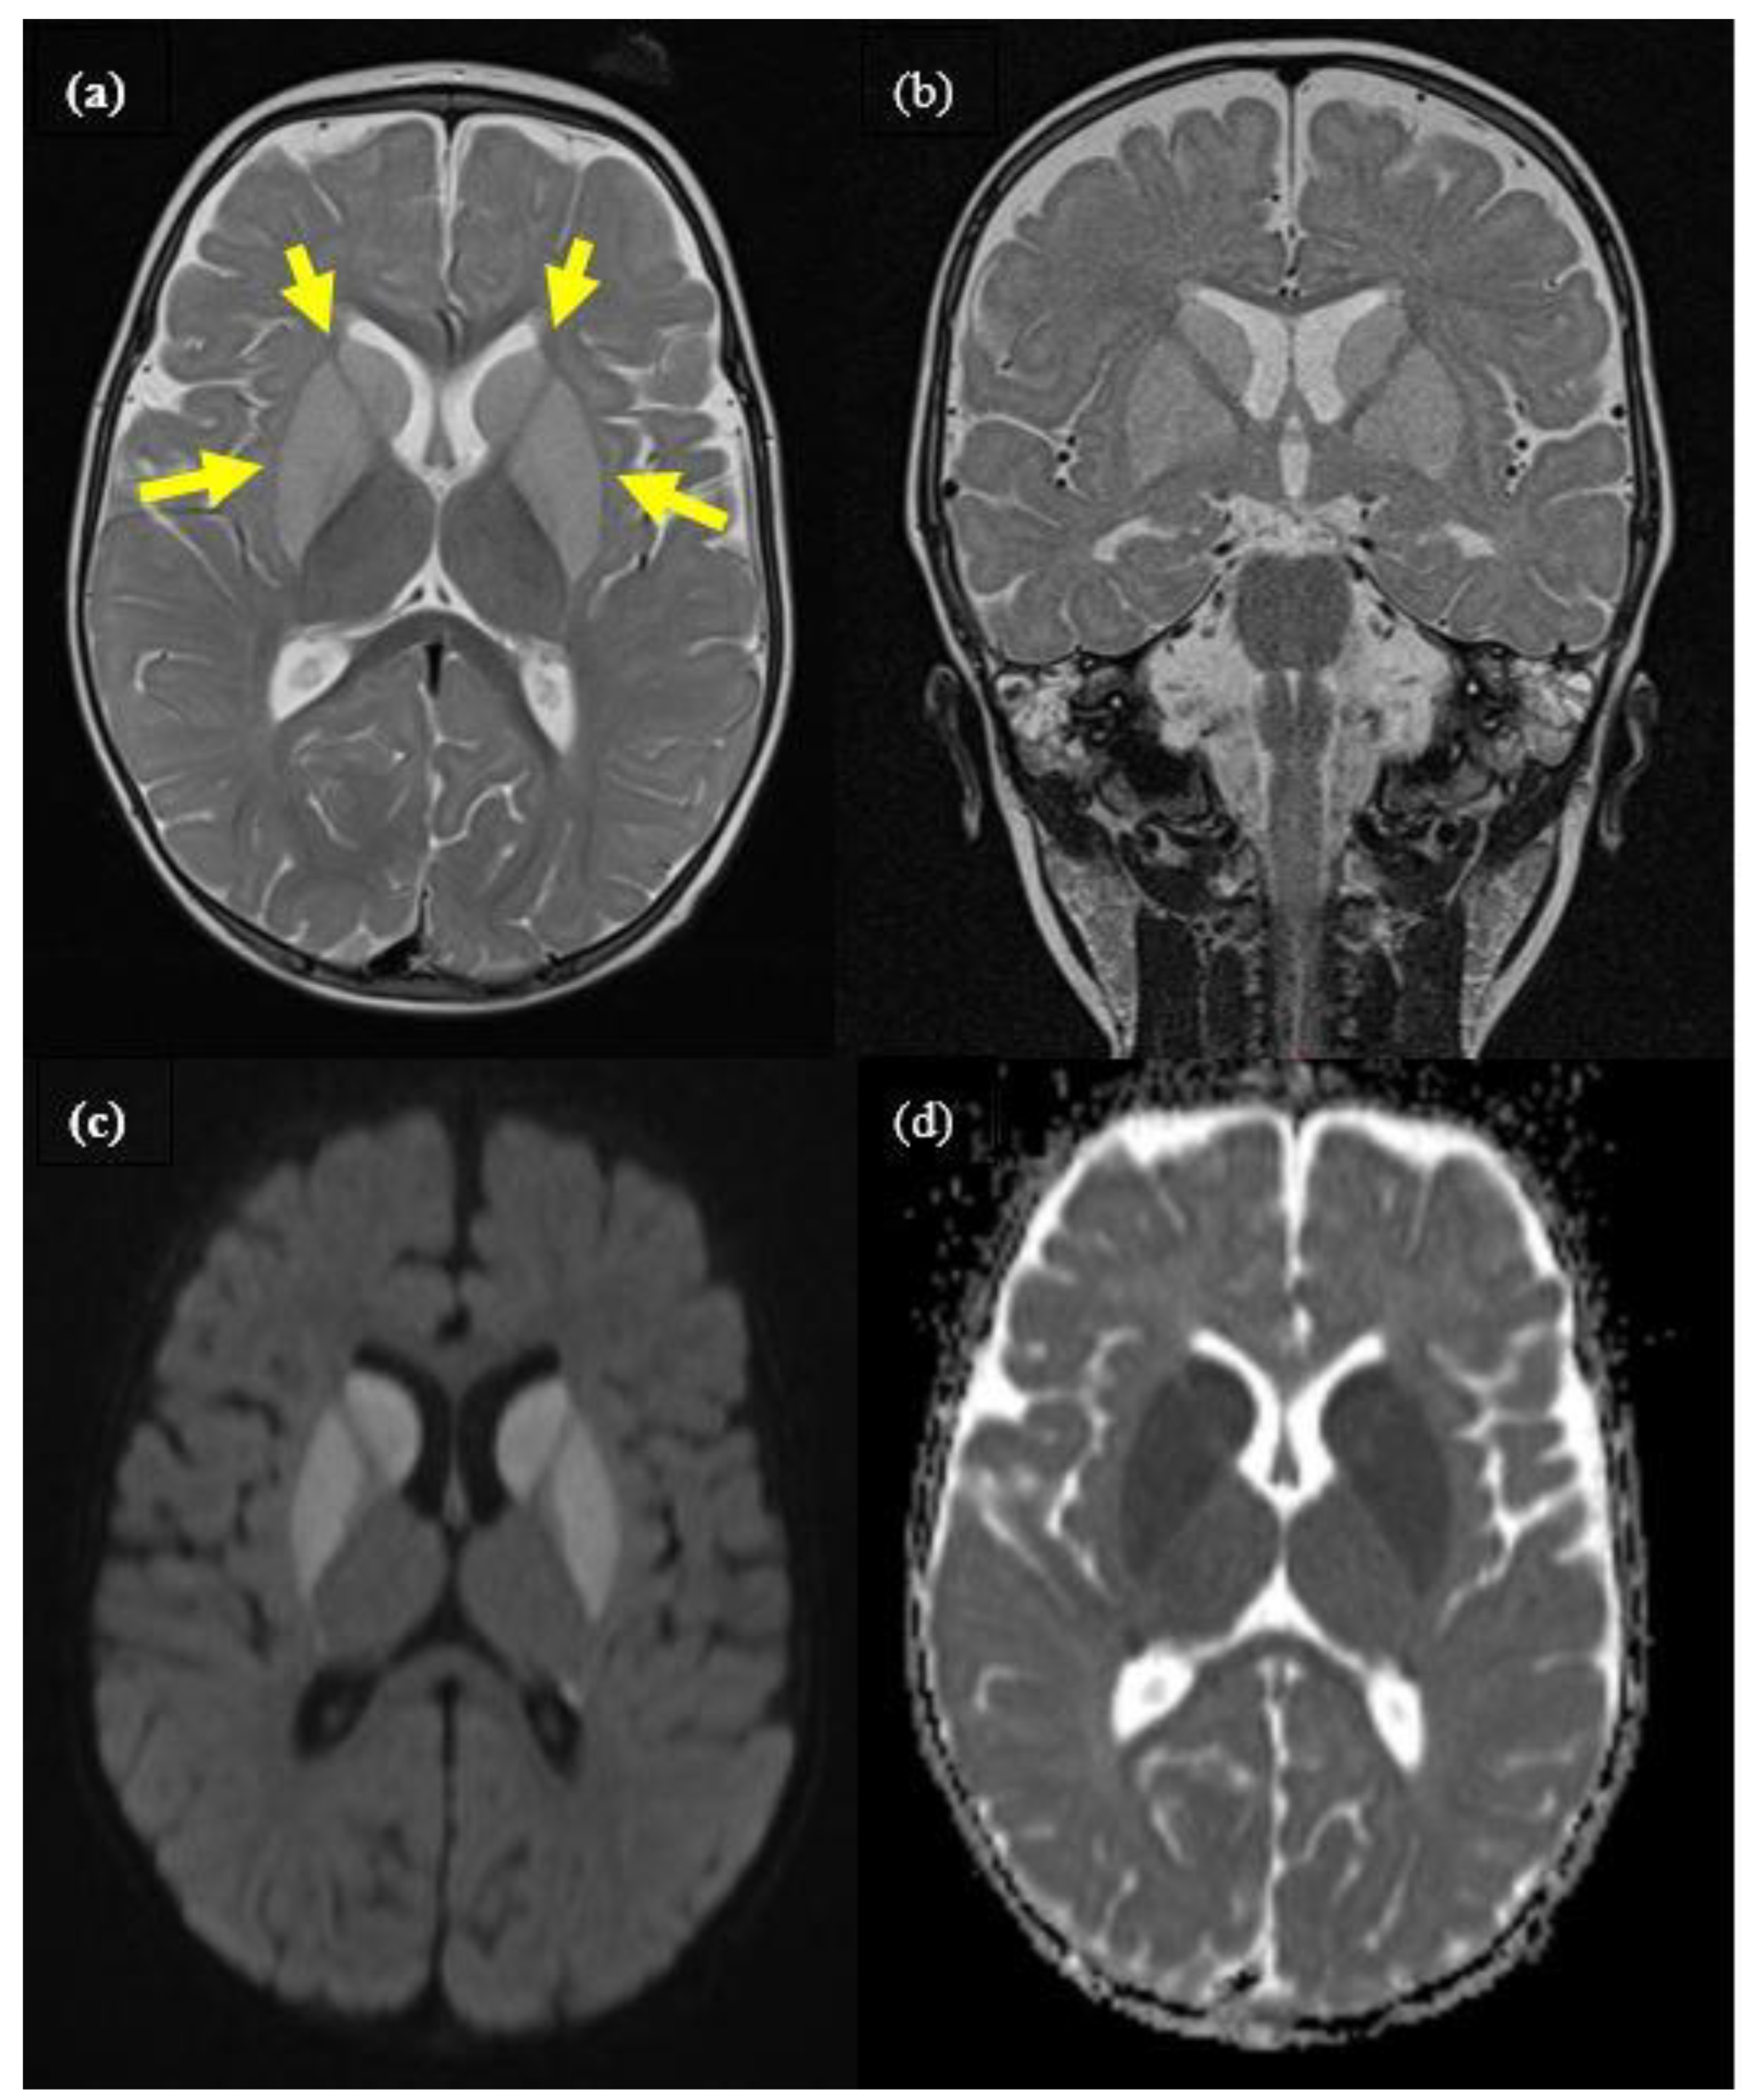

2.1. Case 1

2.2. Case 2

2.3. Case 3

2.4. Case 4